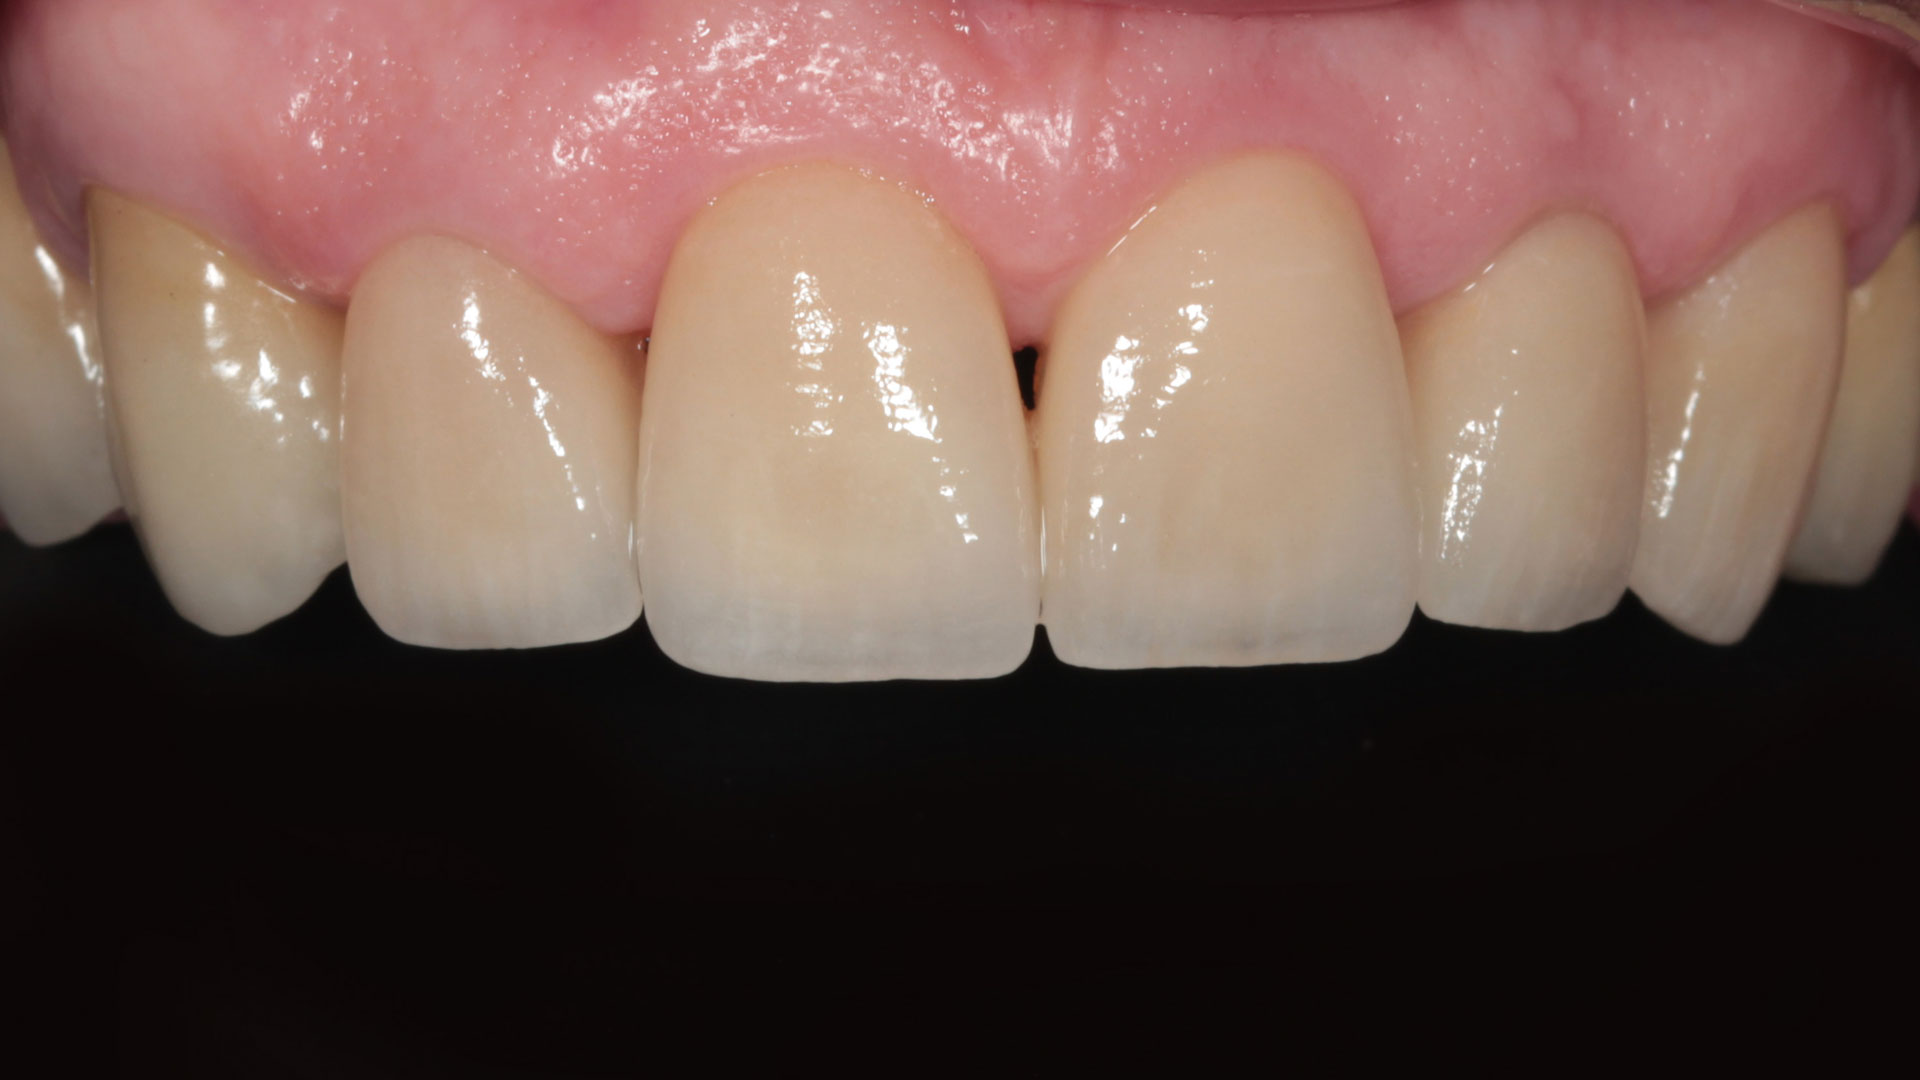

FACCETTE DENTALI

La sottile differenza.

Per migliorare l’aspetto del sorriso, renderlo più luminoso e solare.

- Preparazioni dentali ultra-conservative

- Utilizzo di ceramiche ad alta valenza estetica

SBIANCAMENTO DENTALE

Discromie diverse richiedono diversi sistemi di sbiancamento

Riconoscere il tipo di discromia permette di creare il giusto piano di sbiancamento, dalla sola seduta di igiene orale con lucidatura ad aria, allo sbiancamento vero e proprio con gel sbiancante, fino alla soluzione protesica con faccette o corone.